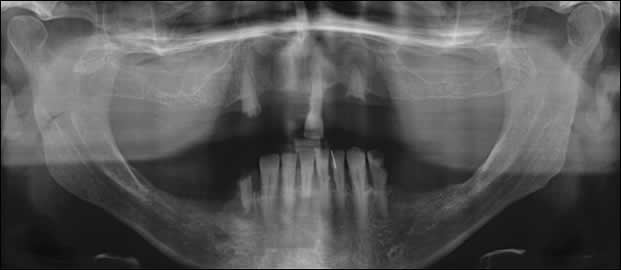

Fig 3: A pre-operative panoramic image demonstrates the missing teeth, tooth decay, residual roots and periodontal disease.